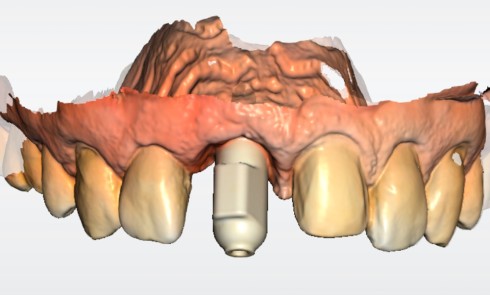

Nous proposons de retirer la couronne et le pilier implantaire, d’effectuer une greffe de tissu conjonctif enfouie afin d’améliorer le volume du tissu kératinisé péri-implantaire [5] et de procéder à la pose d’une couronne provisoire transvissée (fig. 3a à h).